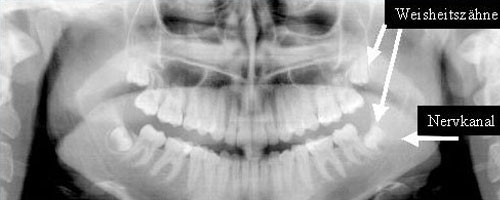

Neben der klinischen Diagnostik reicht in den meisten Fällen eine Röntgenaufnahme in Form einer Panoramaschichtaufnahme (PSA) – auch OPG (Orthomopaantogramm) genannt. aus.

Falls Zweifel über die Lage der Zähne z.B. in Relation zum Nervkanal bestehen, ist eine Schichtaufnahme in der zweiten Ebene notwendig, z.B. durch ein DVT (digitales Volumentomogramm).